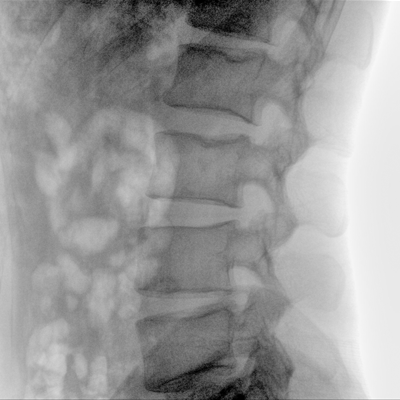

可用于常規(guī)的外周血管介入手術,設備的移動性好,對手術室空間要求低,可滿足長時間X光透視的需求,且增加了獨特的血管影像處理功能,是開展介入手術的理想設備。

優(yōu)質平板探測器、可靈活升降調節(jié)SID、獨特圖像處理系統(tǒng)、高品質濾線柵,大視野成像清晰不失真。

采用智能劑量控制技術,可根據(jù)不同體型和不同部位,準確調節(jié)投照劑量。使操作者在任何使用環(huán)境下,都能實現(xiàn)低劑量、診視圖像清晰的效果。

無需專用機房及動力電源,移動式設計可多科室共同使用,手術室無需改造,無需裝置地軌和吊架,手術室的電源條件滿足220V即可達到安裝和使用要求。